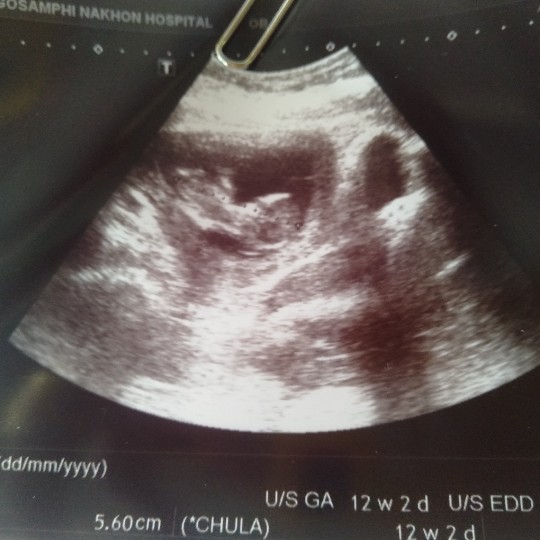

12w เห็นแล้วยิ้มไม่หุบเลยค่ะ

มองไม่ชัดแต่แค่เห็นก็น้ำตาไหล